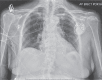

Cardiac memory is a common condition occurring after a period of abnormal depolarization, such as with right ventricular apical pacing. With restoration of normal conduction, the T-wave "remembers" the direction of the QRS vector of the previously aberrantly conducted complexes, creating diffusely inverted T-waves on the electrocardiogram. The presence of diffuse T-wave inversions with this phenomenon may be confused with myocardial ischemia and may continue to be present for several weeks after restoration of normal conduction. Here, an interesting electrocardiogram obtained after pacemaker implantation showing the opposite effect, ie, the finding of memory T-waves occurring during pacing after a period of intrinsic atrioventricular nodal conduction, is presented. In this case, the patient had an underlying left bundle branch block, which subsequently normalized as a result of conduction system pacing. The memory T-waves became evident after pacing was performed, suggesting a potential marker for restoration of the normal ventricular activation sequence with left bundle branch pacing and normalization of the baseline intraventricular conduction defect.